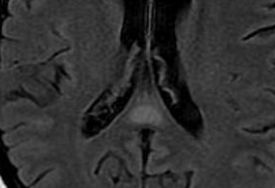

IRM

- HyperT2 / Flair

- Restricte la diffusion en phase aigue

- Souvent les signes de Wernicke-Korsakoff sont absents